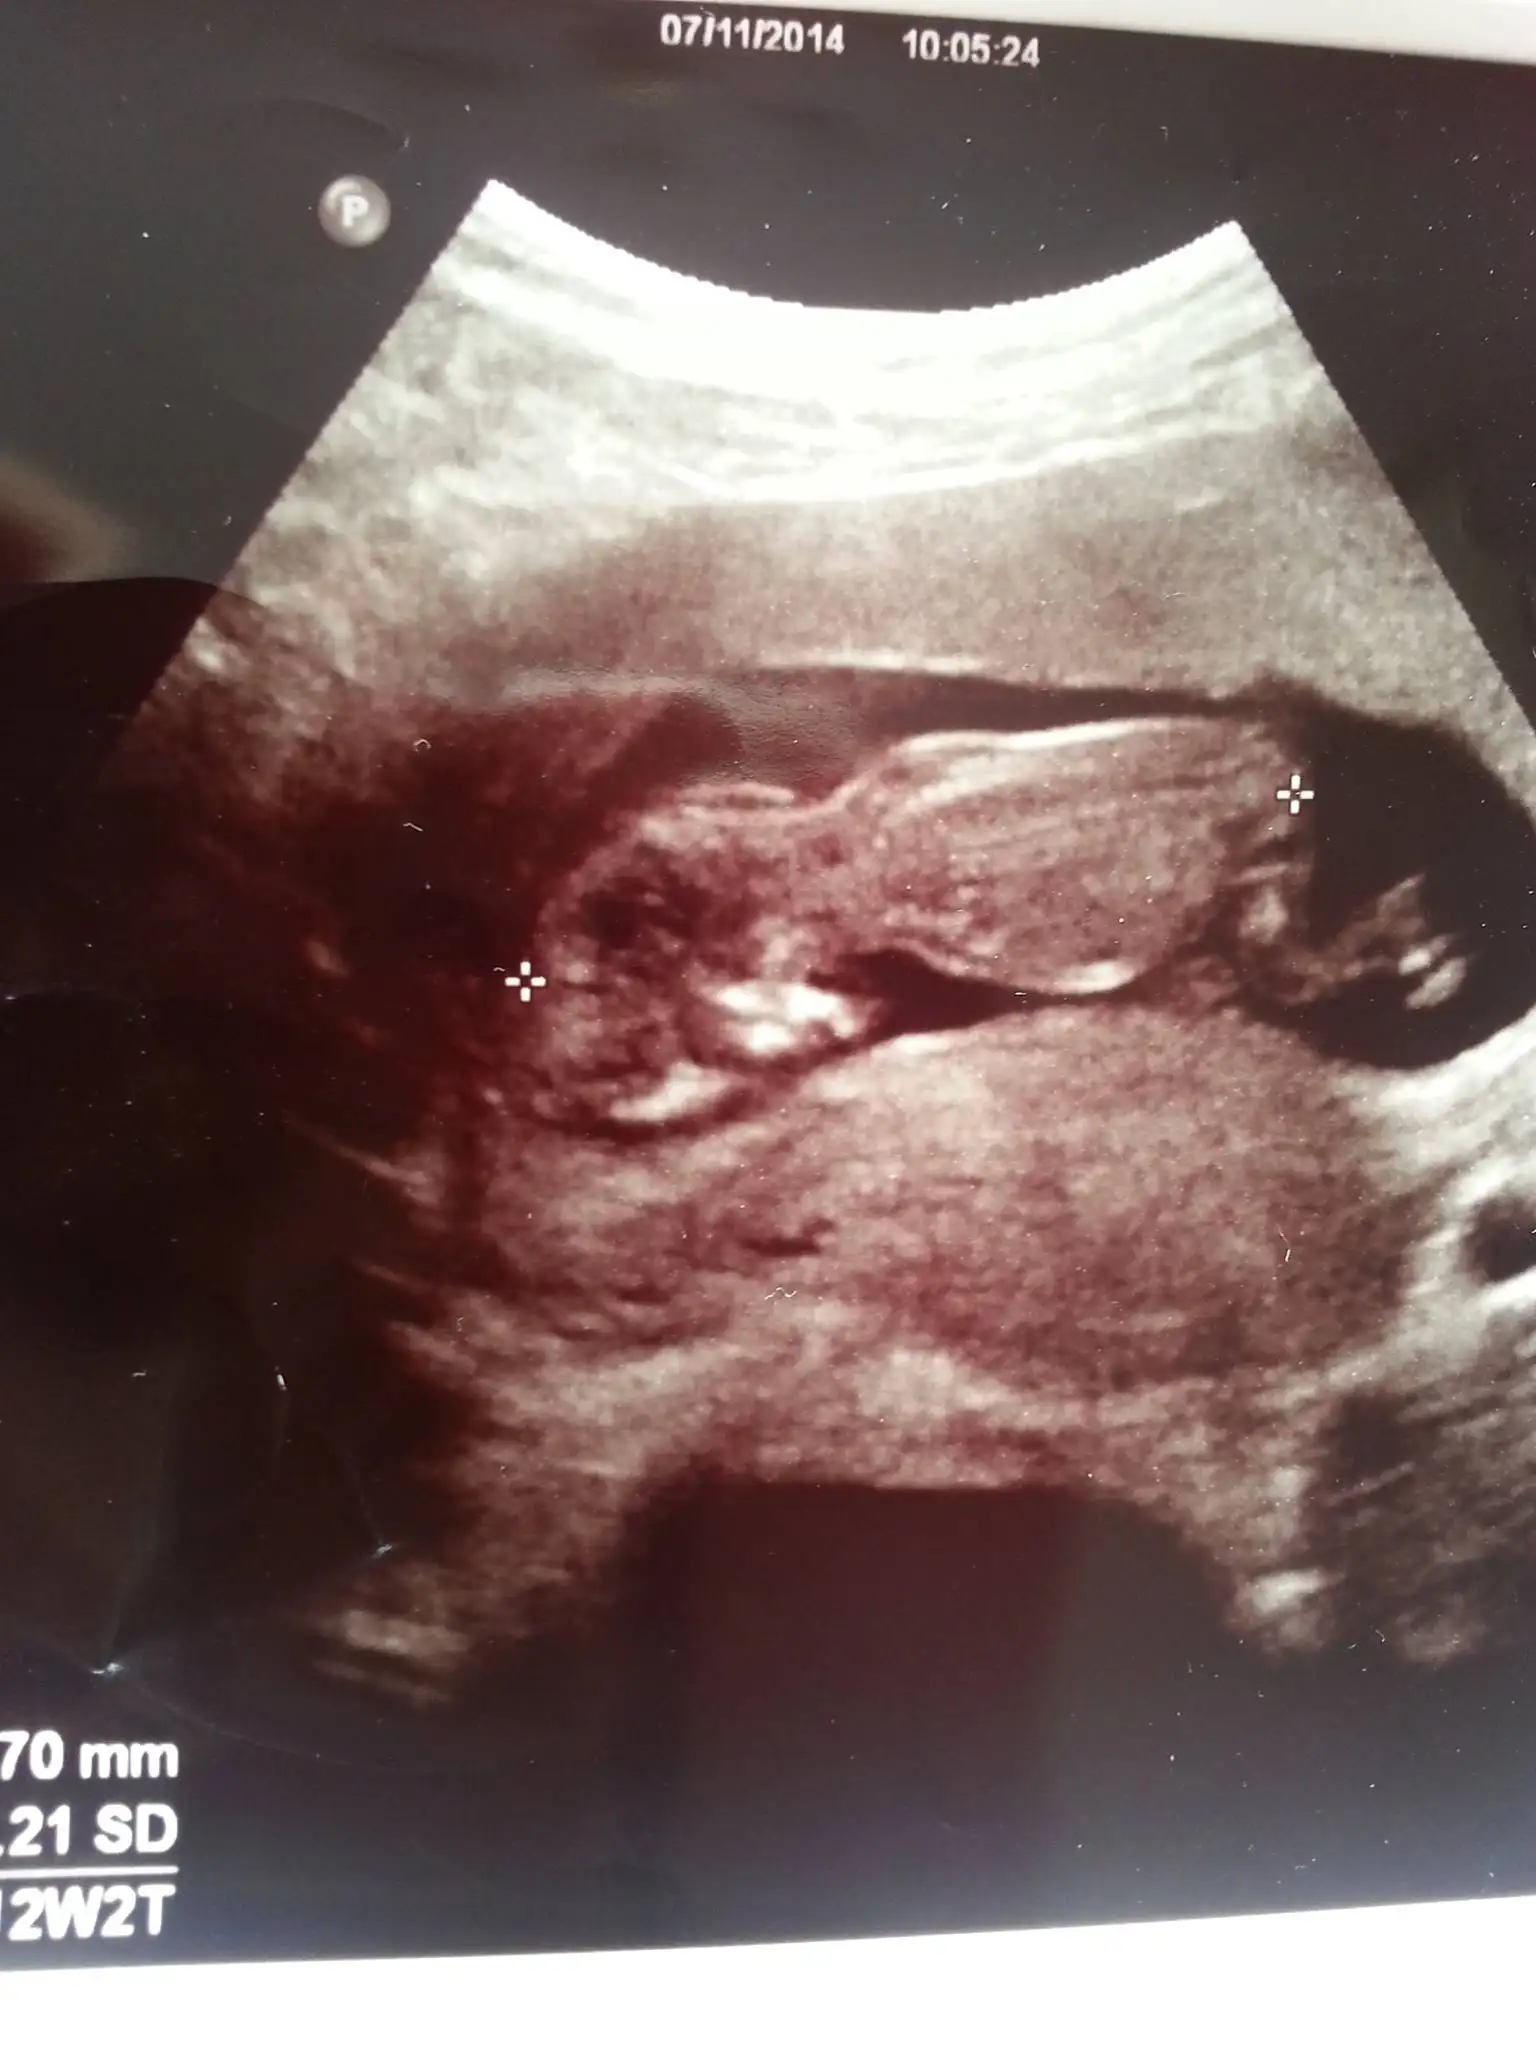

Erkek gibi canim nasilda uzanmis masaAllah:)Kizlar hep bu ani bekledim 12 haftalik teyzeleri bi yorum yapin hadi...

Sagol cnm benim yorumuna... doktor kiza benziyor ama emin degilim dedi acikcasi bende ilk cocugum kiz istiyorum ama erkek hissediyorum cok karistim yaErkek gibi canim nasilda uzanmis masaAllah:)

bence kız bu.nub paralel bir şekilde uzamış.Kizlar hep bu ani bekledim 12 haftalik teyzeleri bi yorum yapin hadi...

maşallah seninki ne güzel gelişmiş.bacakları falan ortada nub,mub kalmamış.direk cinsiyetini görmüştür doktor.erkek olabilir mi acaba bu kadar erken geliştiğine göre.merhabalaaarr...acaba bizim icin de bi thminde bulunabilir misiniz???? 12haftalık goruntumuz...

öyle mi? çok mu gelişmiş? 12 haftalık evet bacakları falan çok belirgindi çapraz yapmış yüzsütü uzanmıştı. doktor daha çok erkek tahmin için dedi...maşallah seninki ne güzel gelişmiş.bacakları falan ortada nub,mub kalmamış.direk cinsiyetini görmüştür doktor.erkek olabilir mi acaba bu kadar erken geliştiğine göre.